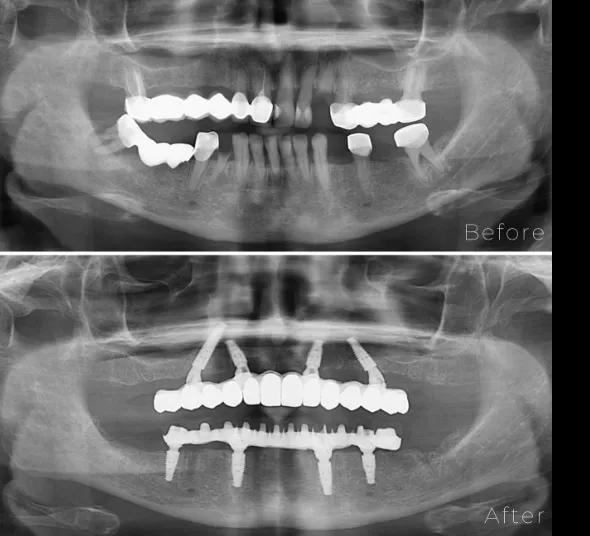

Pacienta Mihaela M., în vârstă de 57 de ani, s-a prezentat în clinică cu lucrări dentare vechi și problematice, edentații și numeroși dinți aflați într-un stadiu avansat de degradare.

În urma evaluării clinice și imagistice, s-a stabilit indicația de extracție a dinților compromiși și realizarea unei reabilitări orale complete prin inserarea a câte 4 implanturi pe fiecare arcadă, utilizând sistemul Neodent NeoArch.

Intervenția a permis aplicarea unei lucrări totale fixe imediate, oferind pacientei o soluție funcțională și estetică încă din primele zile după tratament. Lucrarea finală a fost realizată la 6 luni de la intervenție, după integrarea completă a implanturilor.

Sistem de implanturi NEOARCH

(4 implanturi dentare NEODENT Titan Aqua by Straumann + sisteme protetice + lucrare fixa totala provizorie)

Lucrare protetica finala de tip All-on-4 – infrastructura din TITAN, cu coroane din ZIRCONIU/ arcada